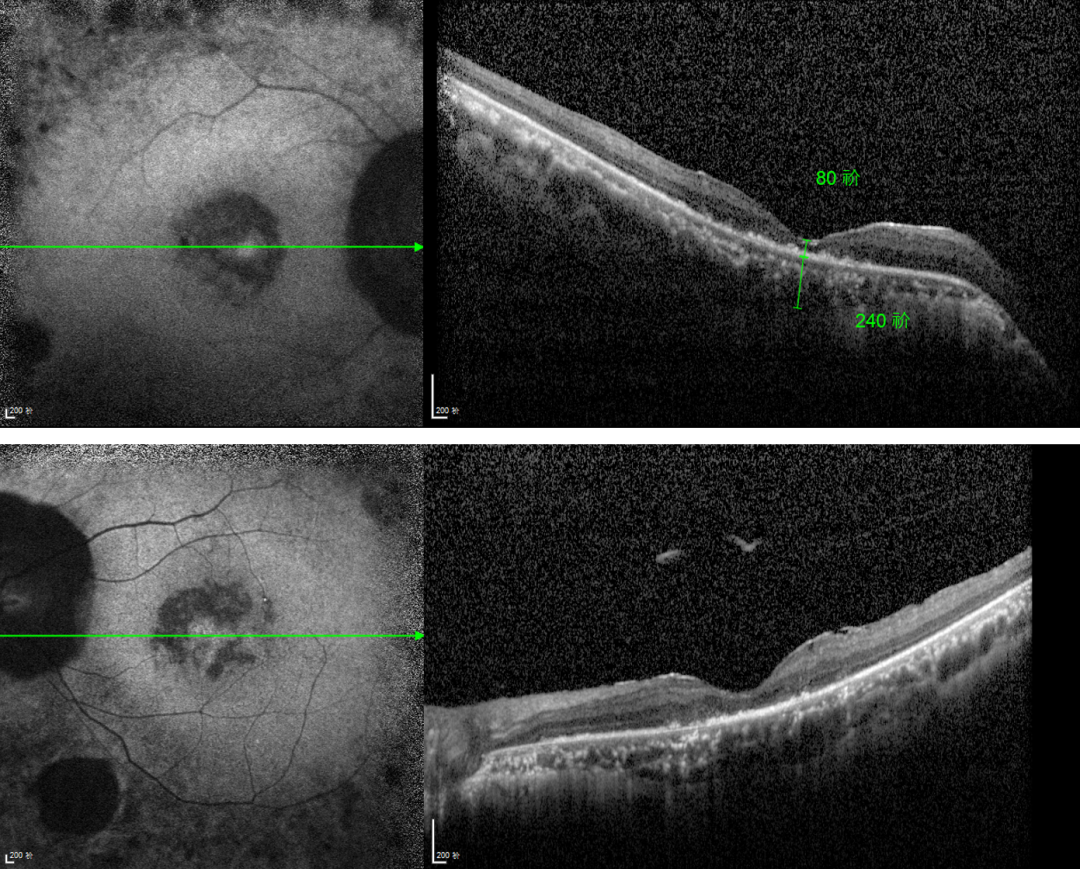

RP的診斷主要依靠眼底檢查、視野檢查、視網膜電圖(ERG)和基因檢測。眼底檢查可見典型的"骨細胞樣"色素沉著,ERG顯示視網膜功能下降,基因檢測可確定具體的突變基因。

視網膜色素變性